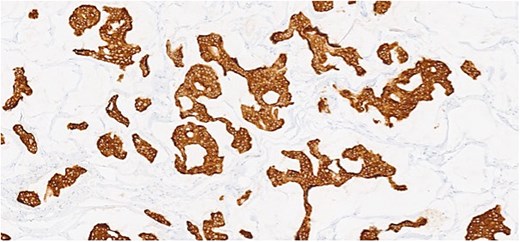

Section showing tumor cells with low to intermediate nuclear grade floating in pools of extracellular mucin separated by fibrous septa.

Herein, we present a 75-year-old man who, having been referred to our service with an inguinal hernia, raised concern about a palpable mass present in his right axilla. The main differential on initial examination was that of a simple epidermoid cyst, and consent was obtained for its removal during his elective hernia repair. Subsequent histology however, revealed a well differentiated MAC. There was extensive involvement of the deep and superficial reticular dermis (Figs 1and 2). Lymphovascular invasion was present. Sweat glands were focally involved by the carcinoma. The differential diagnosis included PCMC and metastasis from other primary sites of MAC such as breast, lung and gastrointestinal. Immunohistochemical profiling was performed on the specimen. CK 7, HER2 (4B5, 3+), GATA3 (strong, diffuse), and P16 (focal, weak) were positive (Figs 3–6). SOX10, CK 20, CDX2, TTF-1, p40, ER, and PR were negative which supported the diagnosis of MAC with either breast or PCMC origin based particularly on GATA3 expression.